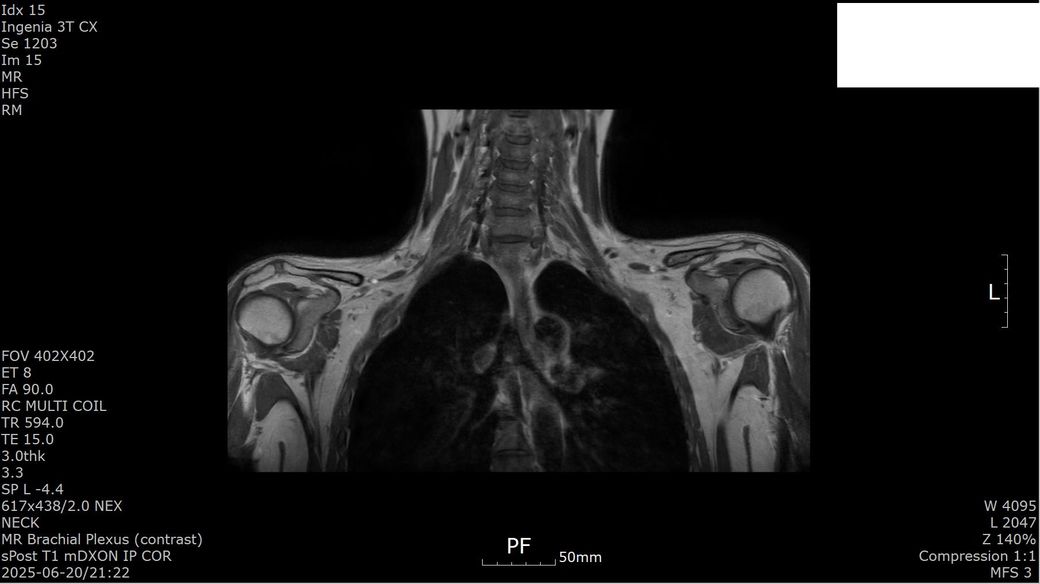

[상완신경총 brachial plexus] mri 판독 부탁드립니다

s/p 2025-01-23

Antereior & middle scalene release, Rt.

1st rib resection, Rt.

Pectoralis minor release, Rt.

Brachial plexus neurolysis, Rt.

2025년 1월경 흉곽출구증후군(우측 사각근 유리술, 우측 제1늑골 제거술, 우측 상완신경총 박리술) 수술한 뒤 5개월 지난 2025년 6월경 상완신경총 mri 검사했습니다.

수술 후 발생한 증상과 mri 소견은 상완신경총 손상 또는 신경 재생 지연에 따른 합병증으로 보입니다.

이두근 위축과 근력 저하는 신경 기능 회복이 아직 진행 중임을 시사하고 감각 이상과 손가락 움직임 제한도 신경 손상의 영향일 수 있습니다. 치료는 신경재활치료, 물리치료, 근력 강화 운동과 함께 신경 재생을 돕는 약물치료가 필요하고 상태에 따라 추가 신경 수술이나 재활적 중재가 고려될 수 있습니다!